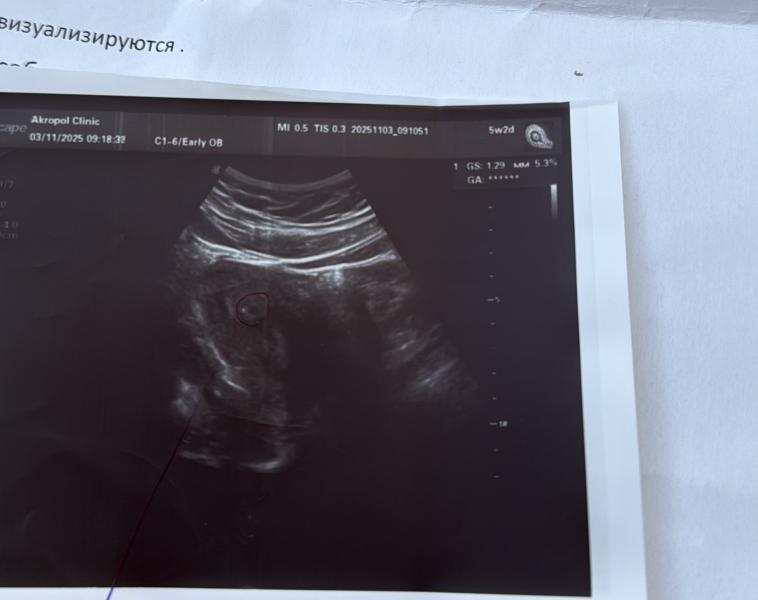

Мой малыш 🥲